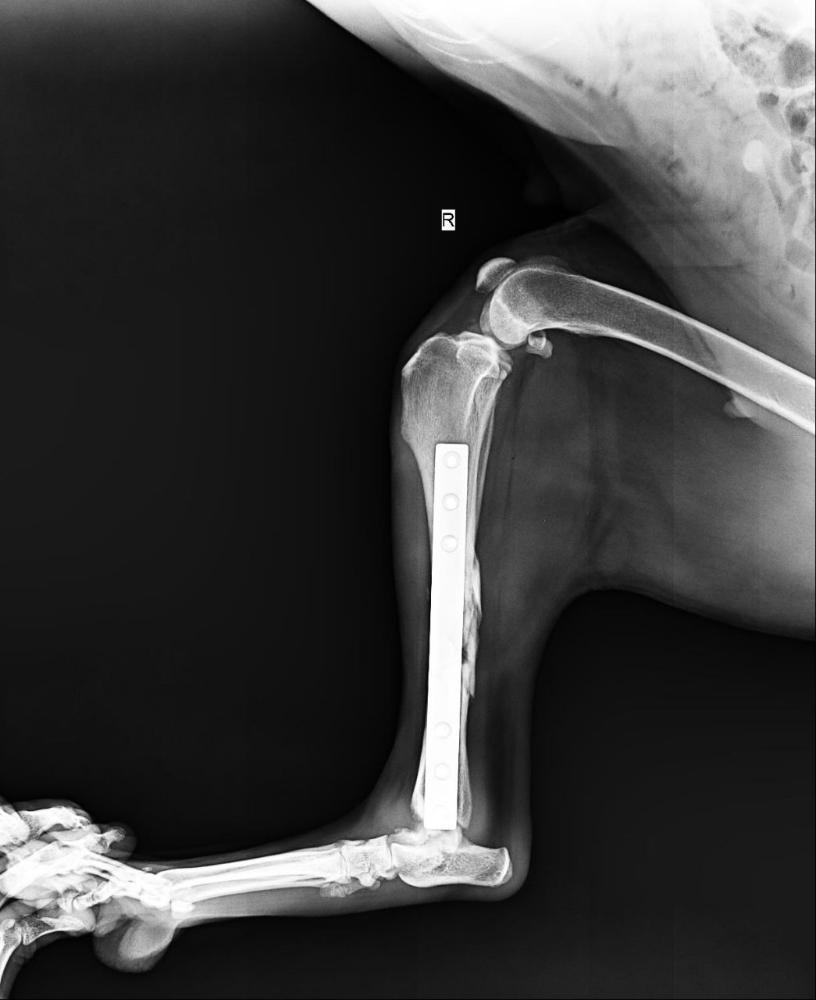

wina Опубликовано 18 января Опубликовано 18 января (изменено) Сдали анализ мочи, расход 900 р, показатели в норме. И- важно- были в клинике Еремина, Док сказал, все хорошо. Лапа собрана на трехмиллиметровой ( в толщину) пластине и 6 штифтах. Док сказал, хорошо, что удалось сохранить длину лапы (!!) , Нора нормально наступает. Остеогенон пить еще месяц хорошо бы. Расход ( рентген) + осмотр 2350. Изменено 18 января пользователем wina 3 4

Светлана 2101 Опубликовано 18 января Опубликовано 18 января Как красиво всё сделано Мастером! Будет бегать девчонка. 3